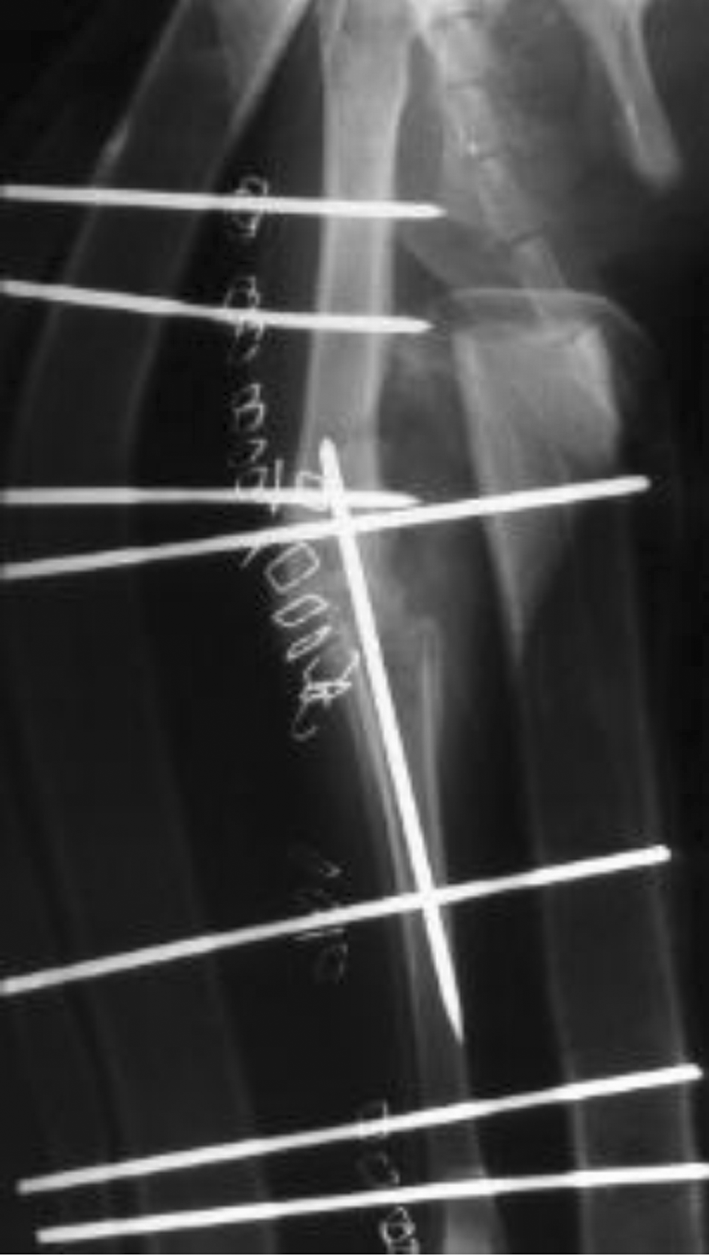

- Verplaatsen van de beenkam op het onderbeen, hierdoor wordt de knieschijf meer naar buiten getrokken waardoor hij gemakkelijker in de sleuf van de femur blijft.

-

- pijltje wijst de verplaatste beenkam aan

- In erge gevallen worden alle drie de technieken op dezelfde knie gebruikt.